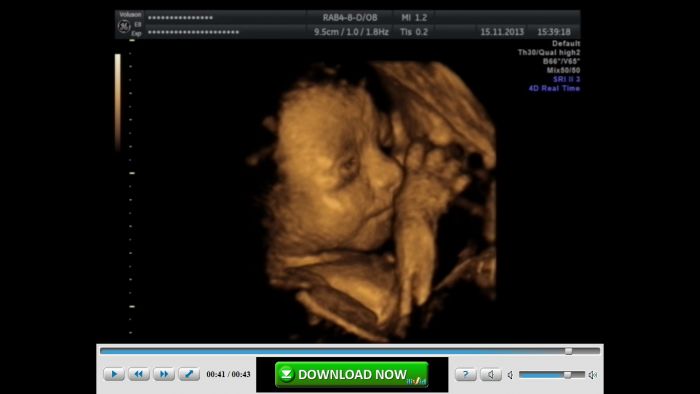

V pátek jsme byli n 4D ultrazvuku a od té doby se naší malé Elišky nemůžu dočkat. Přikládám fotečku.

Evičko, fotka je krásná. My na ultrazvuku nebyli, ale už se taky nemůžeme dočkat. Z jedné strany to letí a z druhé strany si všechny přejeme mít už je doma. :-) S těmi vánocemi to sletí. Taky bych měla začít prát a žehlit. Jinak už máme asi všechno kromě matrace do postýlky a kosmetiku chci pořešit až v prosinci...